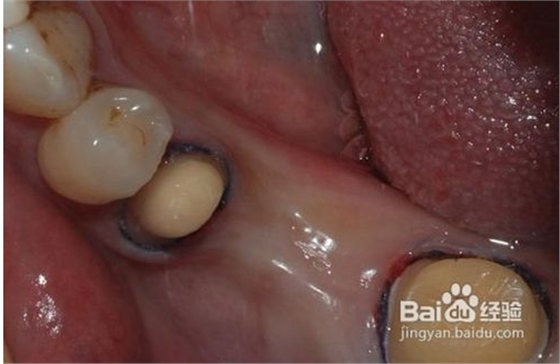

1、磨牙

為了使完成后的烤瓷牙冠戴入后不超過(guò)原始狀態(tài)的外牙厚度,一般做烤瓷牙要磨除部分自然牙。另外為了使假牙順利就位并獲得良好的固位,要將基牙制備成一定的形狀?;乐苽涞暮脡?,關(guān)系到假牙是否容易戴入以及牢固性。

4、試戴粘接

大約1周后制作的烤瓷牙即可完成。首先經(jīng)過(guò)試戴,檢查肩臺(tái)的密貼性,即冠邊緣適合性要符合標(biāo)準(zhǔn),顏色是否一致,形態(tài)是否美觀,以及鄰接關(guān)系,咬合關(guān)系等。如果確認(rèn)沒(méi)有問(wèn)題,醫(yī)生通過(guò)特殊粘接劑,粘接在預(yù)修復(fù)的牙體上,烤瓷牙的修復(fù)工作全部

完成。